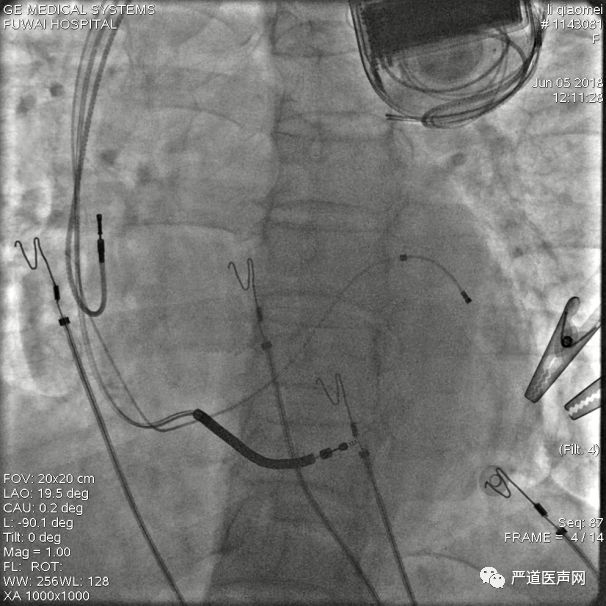

“双泥鳅”法进入冠状窦主干

将一根泥鳅留在后静脉内作为支撑,回撤长鞘至冠状窦口,使用另一根泥鳅按造影显示进入冠状窦主干

将长鞘送入冠状窦主干

顺利找到冠状窦主干,将两根泥鳅都送入主干内加强支撑,再送入长鞘

冠状窦十极电极仍无法送到远端

尝试将冠状窦十极送到远端有阻力,反复尝试失败

回放造影,可见侧静脉及冠状窦主干显影,主干无明显狭窄,考虑侧静脉开口前有瓣膜阻挡

尝试使用泥鳅导丝通过瓣膜部位

再次放入泥鳅导丝,通过瓣膜部位到冠状窦远端

鞘中鞘经泥鳅导丝,通过瓣膜部位

鞘中鞘搭在靶静脉口